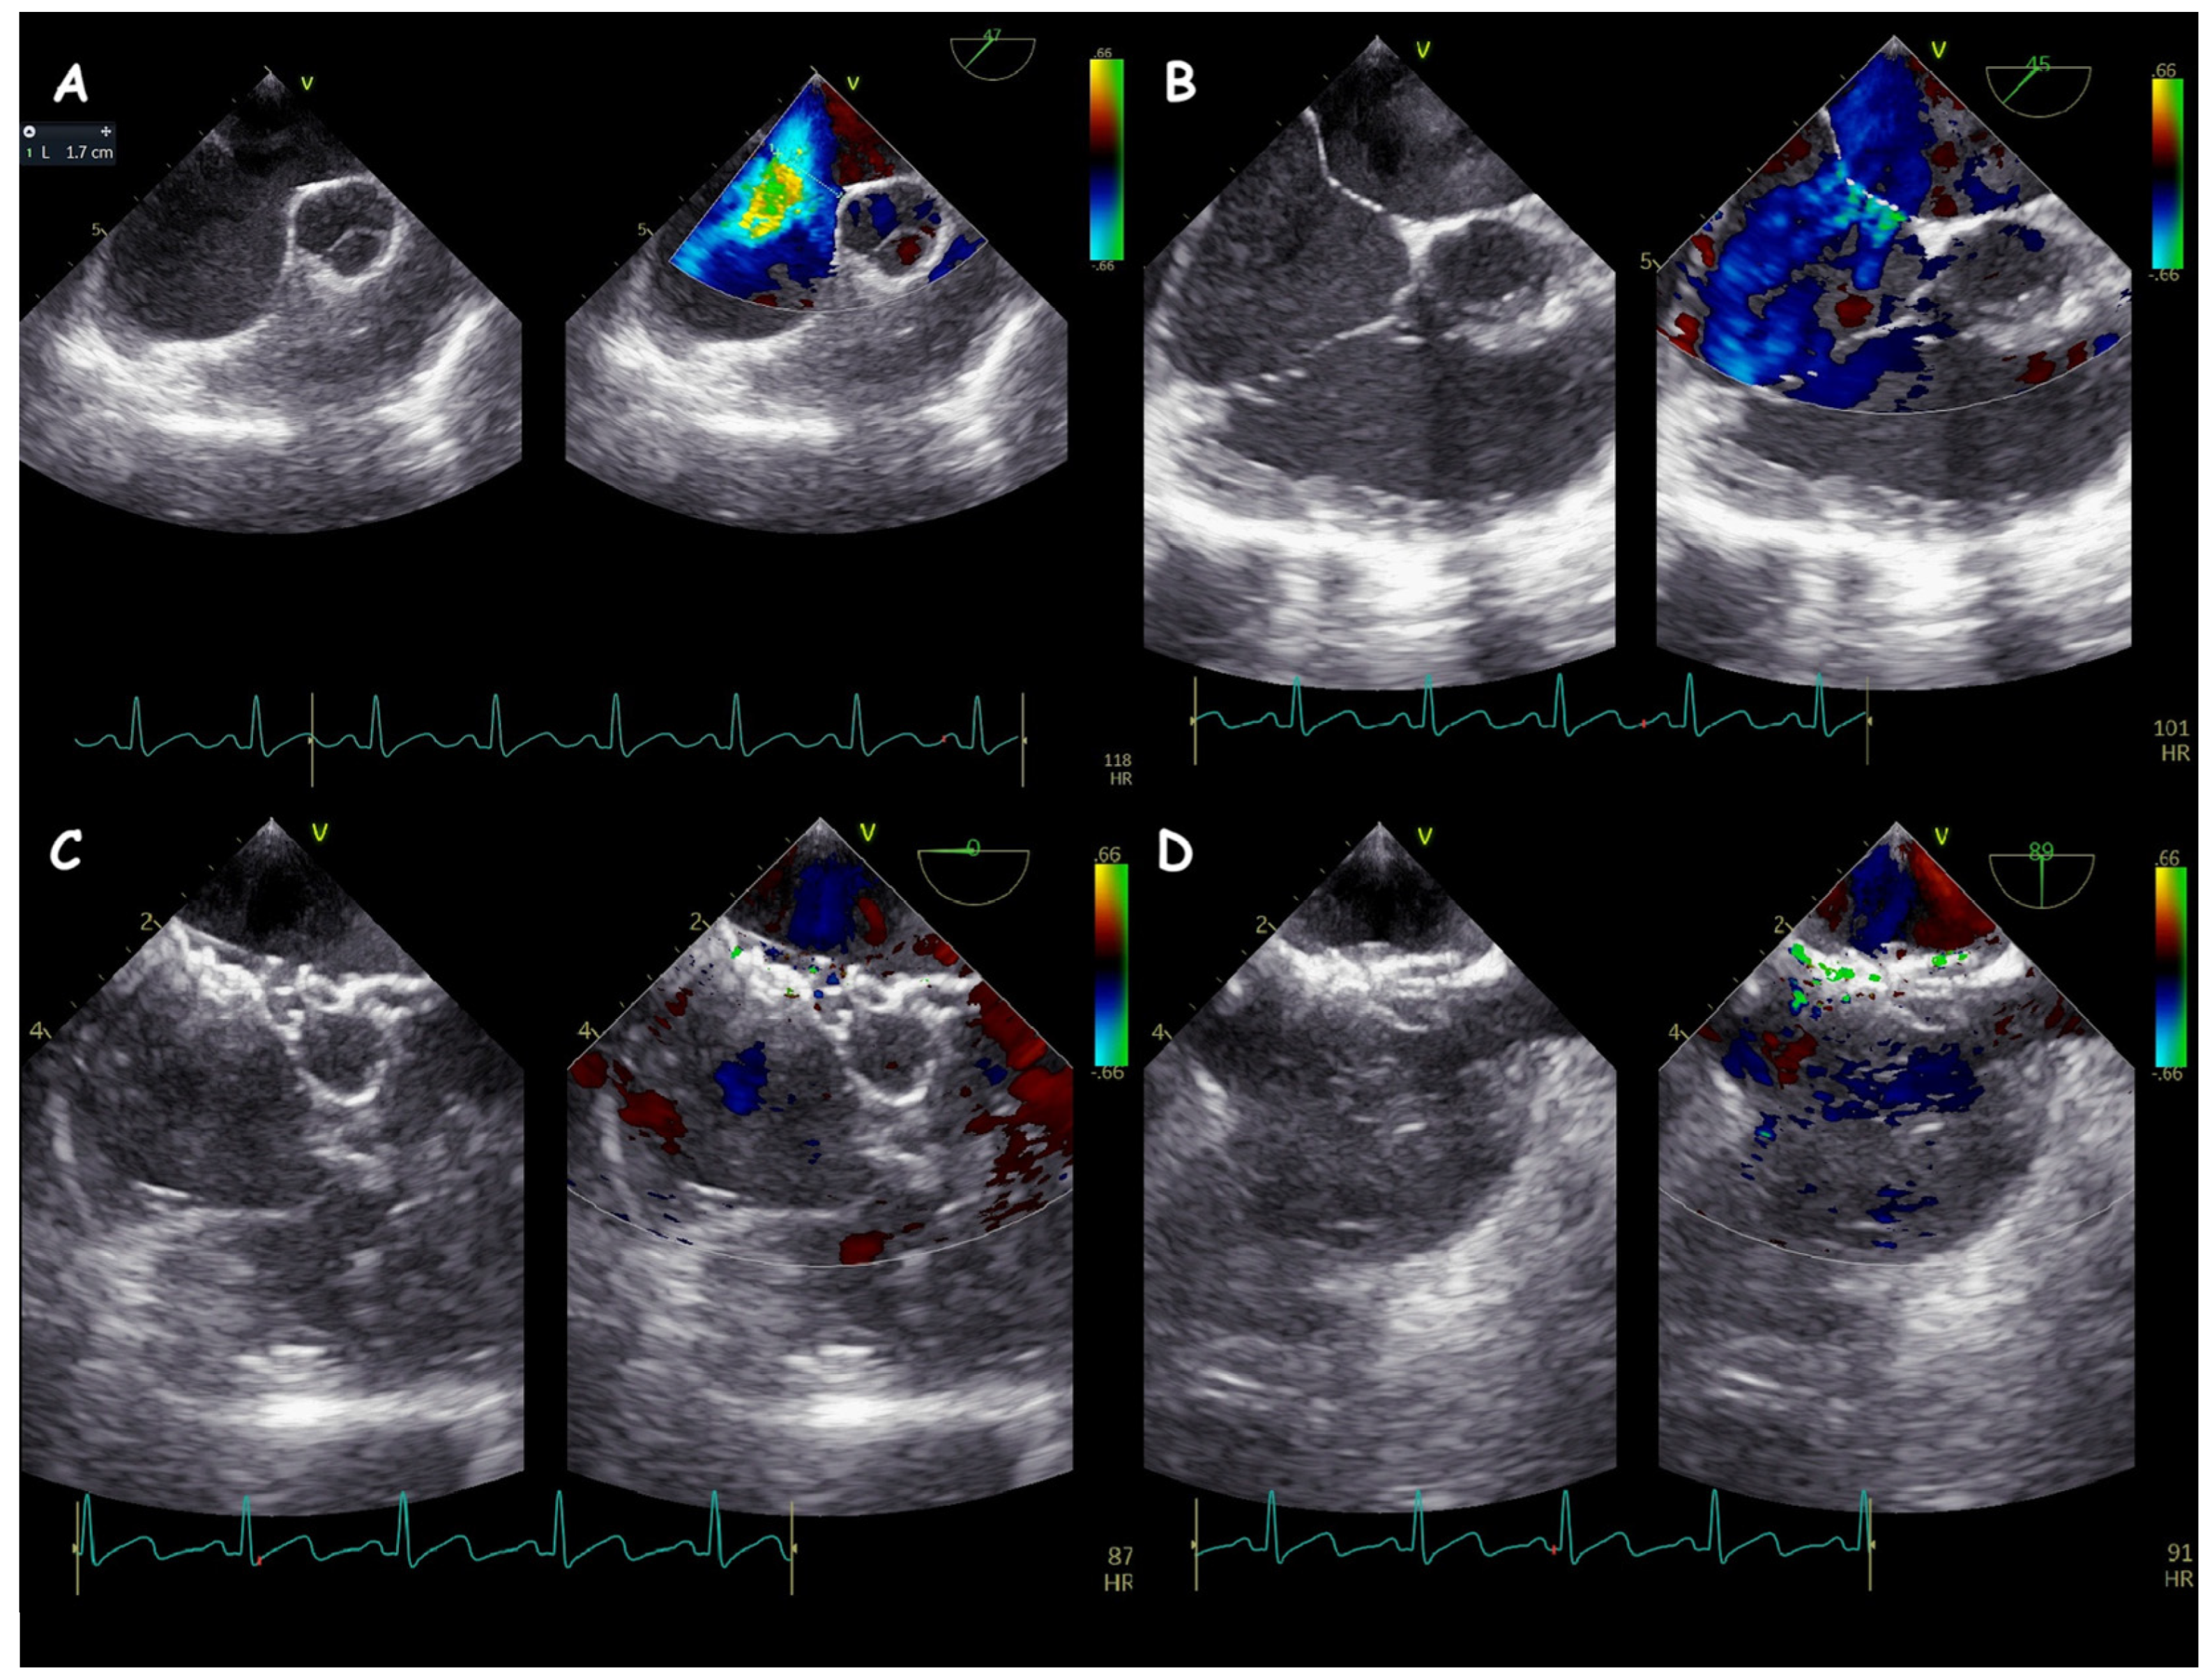

2. Atrial Septal Defect Closure

| ASD Closure: Pre-Procedural Assessment | |

|---|---|

| ASD shape | elliptical, round or irregular shapes (star-, reniform- or other irregular shapes), internal seedings |

| ASD size | maximum ASD diameter |

| ASD shunt direction | left-to-right, bidirectional, or right-to-left |

| ASD periorificial rims | adequate (>5 mm), poor (<5 mm), or absent |

| Accessory ASDs | numbers, size, and distance (if present) |

| Atrial septum aneurysm | base width and an aneurysm excursion into the right or left atrium (if present) |

| Misaligned ASD | distance of separation between the septum primum surface and the septum secundum one (if present) |

| Double atrial septum | separation between the left atrial and right atrial rims of the defects (if present) |

| Redundant Eustachian valve | length and excursion (if present) |

| Chiari network | width and extension (if present) |